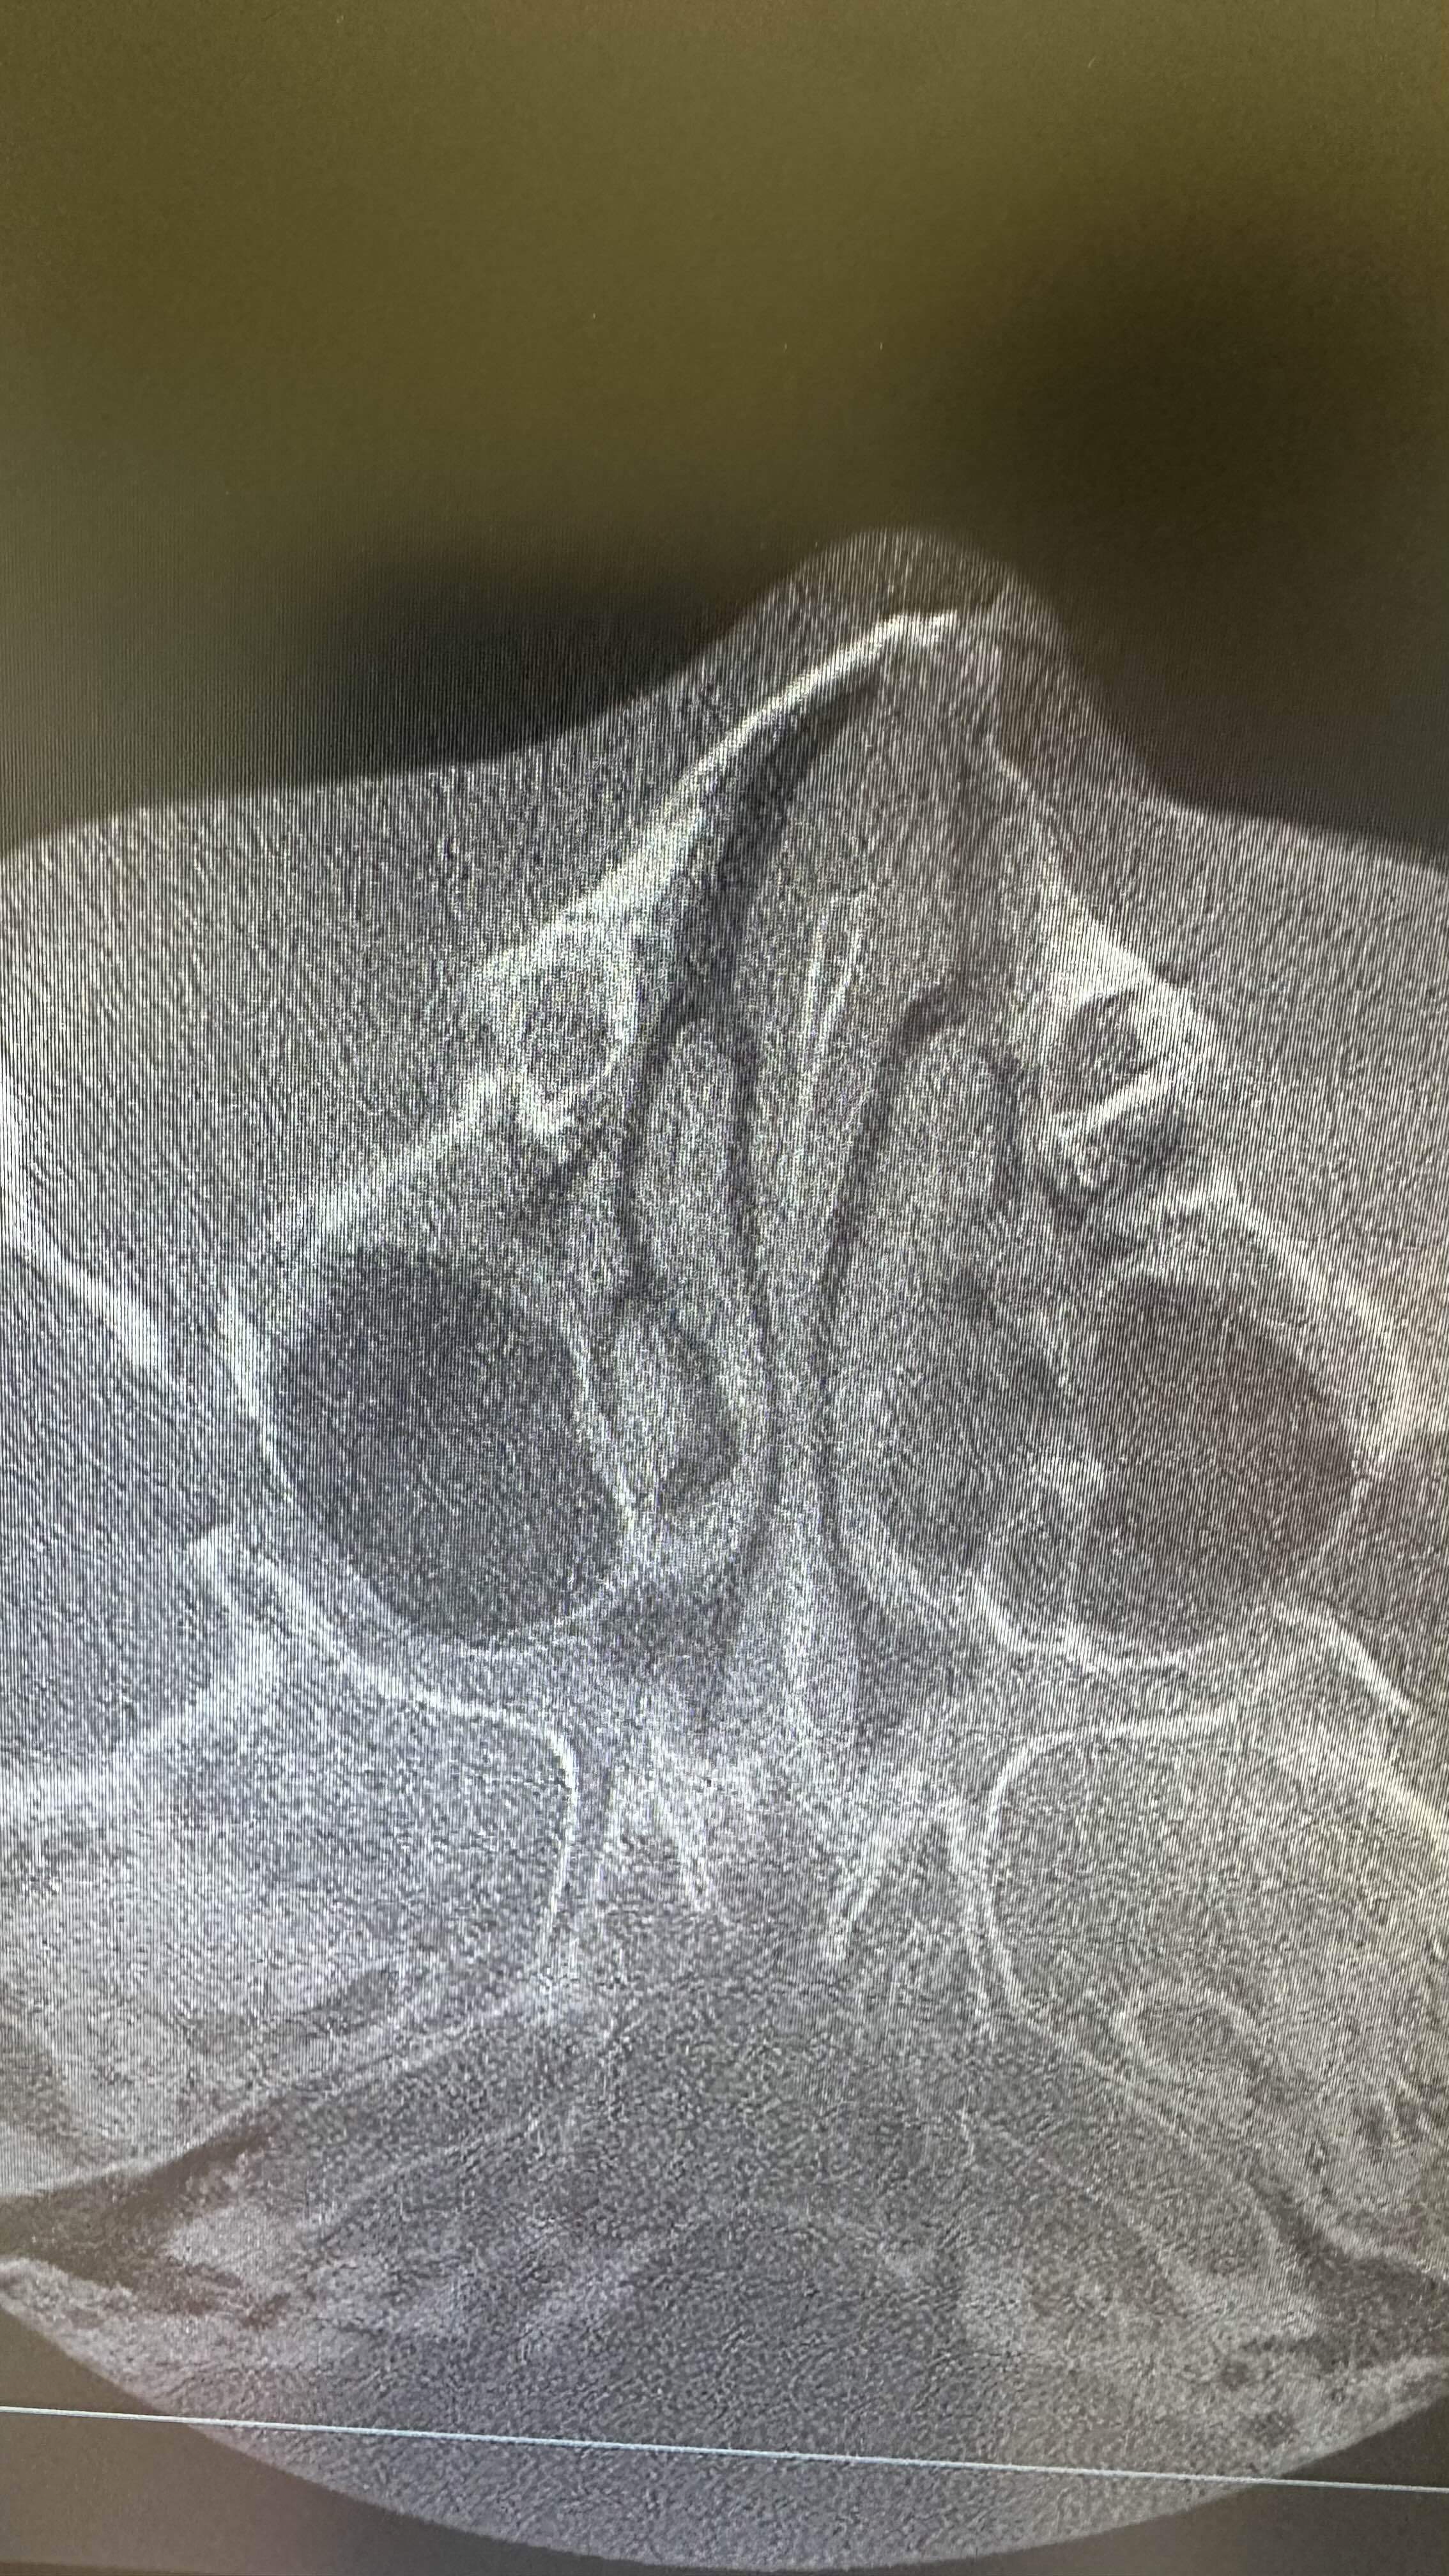

병원에 가서 엑스레이 찍어보니

그냥 호들갑 떨었다는 것으로 판명나서

연고 바르고 진통제만 받아왔어요.

한국에 와서 CT를 찍어보니

3조각 이상으로 부서졌다네요.

의사샘 말로는 박살났다고 ㅠㅠ